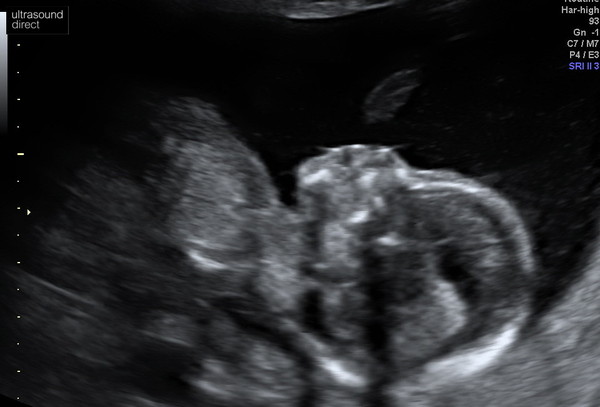

MumOfMiracles · 07/04/2021 20:29

My beautiful girl! Had a private scan tonight and she is doing great! Happy, healthy little baby. 🥰

Looks like cutie pie! x

Great to have it confirmed that we are expecting a girl. 🥰